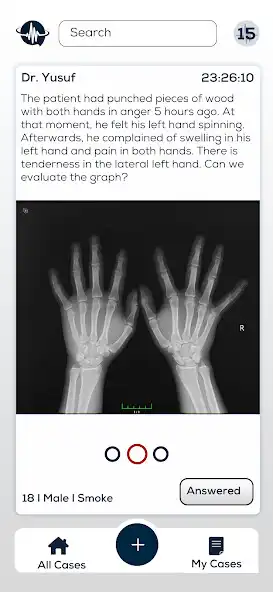

Get Answers to Your Questions in 1-5 Minutes with Live Expert Physician Support.

Did you know that 79% of the diagnostic errors made by General Practitioners(GPs) in the medical process are made during the practice period? - (WHO/2016). This means that more than 5 million GPs need assistive systems. For Physician does not leave the GP alone on duty. It provides the GP the opportunity to consult the patient in seconds. It offers 24/7 online specialist physician support. It provides the opportunity for continuous education by accessing the cases of all physicians. It provides the correct diagnosis and treatment approach. It gives the opportunity to improve the health service it offers to its patients.